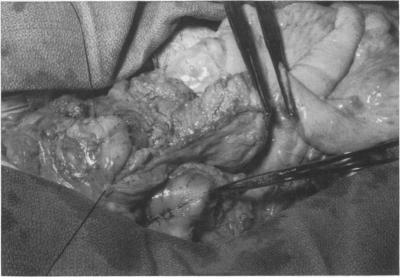

Palliative operation for carcinoma of cervical and thoracic esophagus.

Ann Surg. 1971 May;173(5):714-32. doi: 10.1097/00000658-197105000-00012.